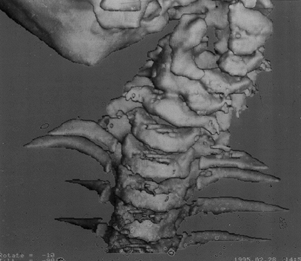

instability (Fig. 158.6).

Figure 158.6. A: A 15-month-old child with metatrophic dysplasia and painful torticollis. The head is kept in marked hyperextension. B: Lateral roentgenogram shows some anterior C-1 displacement with rotation and stenosis. C: CT-myelogram confirms rotational malalignment and stenosis. D:

Posterior C1–C2 decompression and occiput to C-3 fusion done by the method of Koop. Wires seen are through facets (Southwick type). Tibial graft is used. Unfortunately, the patient died 3 months postoperatively due to the restrictive lung disease associated with metatrophic dysplasia. |